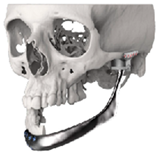

| 9 | 52 | FT-M0 | ![]() | Temporal bone, zygomatic arch, glenoid fossa extended medially and condyle | Cobalt-chromium-molybdenum alloy backing capping the UHMWPE fossa | Cobalt-chromiun-molybdenum alloy | Skull component: 82.3 mm titanium screws. Manibular component: 82.7 mm titanium screws |